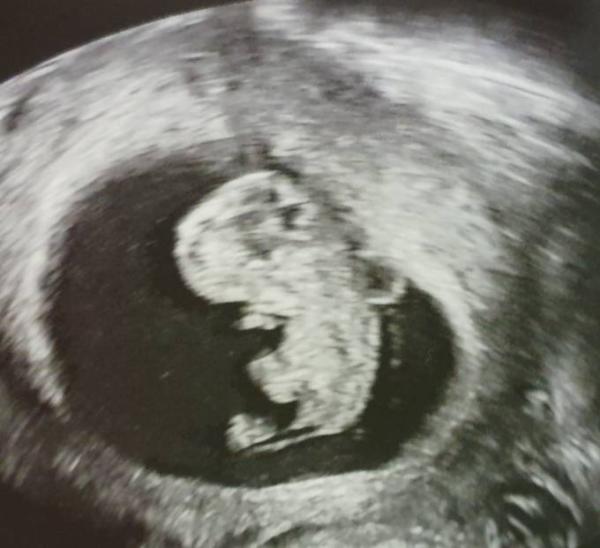

Hallo, ihr Lieben. Ich bin noch eine recht stille Schreiberin, trotzdem wollte ich mein Glück mit euch teilen. Die letzten 4 Wochen waren eine Achterbahn der Gefühle wie das viele von euch kennen. Heute der ersehnte 2. Ultraschall mit meinem Freund,er wird das erste Mal Papa und war genauso aufgeregt wie ich. Es war unglaublich schön und ich bin so erleichtert. Dem Würmchen geht es gut,mir kamen die Tränen vor Erleichterung und nach langen Überlegen hat die Ärztin uns von 11+1 auf 10+5 datiert. Alles egal hauptsache es ist gesund.

Bild zu Unbeschreiblich... - Forum für April - Mamis